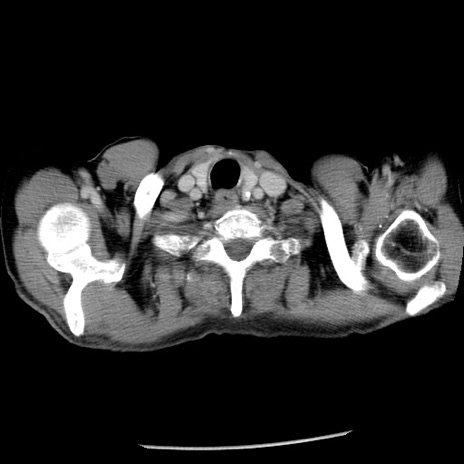

症例26(横断像)

【症例】80歳代男性

【主訴】嘔吐

【現病歴】昨晩2回嘔吐あり、今朝になっても嘔吐あり。来院。

【既往歴】胃潰瘍

【身体所見】意識清明、BT 37.6℃、BP 166/95mmHg、HR 100bpm、SpO2 97%、腹部:平坦・軟、腸蠕動音聴取良好、圧痛なし。

【データ】WBC 21900、CRP 1.46